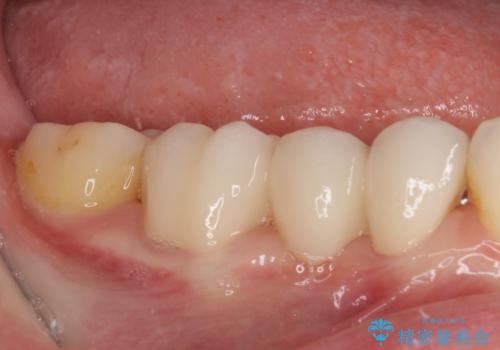

矯正治療自体はインビザラインで満足のいく仕上がりとなりました。

前歯は根管治療が必要となり、元々舌側に入り込んでいた左上2番目の歯は歯周外科処置により歯肉ラインを整えることとしました。

欠損部位は傾斜歯軸を起き上がらせることができたため、オールセラミッククブリッジにて補綴治療を行いました。

全顎的に満足のいく仕上がりとなりました。